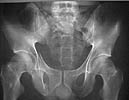

AP Pelvis

A 28 year old male jumped from the 4th floor on 11-25-2000 sustaining an L1 burst fracture that has been fixed anteriorly by the neurosurgeon with a strut between T12 and L2. A Kaneda device was placed anteriorly as well. My concern is the pelvic ring injury. There are bilateral sacral fractures through the foramen and a transverse element through the sacrum between S2 and S3. the lower part of the sacrum is displaced forward. Anteriorly there are right superior and inferior pubic rami fractures.

"H-shaped" sacral fractures are the combination of a "U" with associated bilateral pelvic ring injuries...analogous to a "Y" with associated bilateral ring injuries...fortunately, rarely are both hemi-pelves clinically unstable.